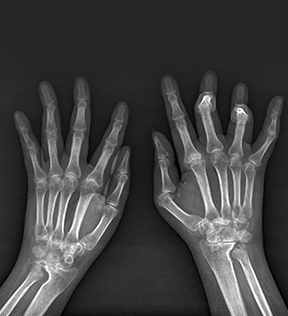

손가락관절염

손가락관절염은 손가락 관절에 염증이 생겨

손가락 운동 제한과 통증을 유발하는 질환을 말합니다.

다양한 원인으로 발생하지만, 노화로 인해 손가락 관절이 닳아지는 퇴행성 변화와

자가면역질환의 하나인 류마티스관절염 등이 주된 원인으로,

퇴행성 변화로 인한 경우 가족력이 있거나, 손가락을 무리하게 반복하여 사용하는

직업군에서 발병률이 높습니다

손가락관절염 주요증상

- 손가락을 움직일 때 소리가 나는 경우

- 손가락 마디가 두꺼워지거나 변형

- 손가락 마디가 뻣뻣하며, 붓고 통증이 발생

- 손가락을 굽히거나 펴는 것이 불편하며

통증이 느껴짐

- 아침에 손이 부어있고, 통증이 있으며

손바닥에 홍반이 보임